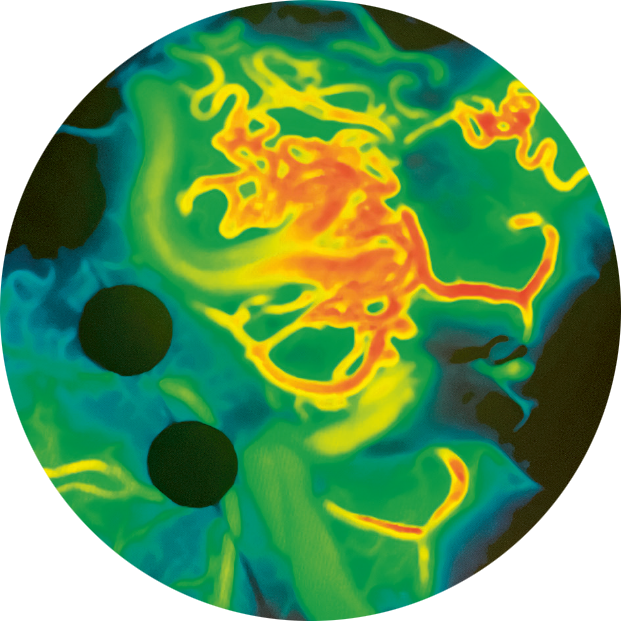

Dans ce bloc opératoire de neurochirurgie, des écrans partout ou presque… et une impression de science-fiction. À l’image : le zoom sur l’intervention chirurgicale en cours, visant à retirer une malformation artérioveineuse nichée dans le cerveau de la personne endormie. Soudain, sur les écrans, des «objets virtuels» – créés à partir d’images du ou de la patiente elle-même – s’imbriquent avec les structures anatomiques réelles, avant d’être rejoints par des éclairs de fluorescence. Leurs flashs indiquent en temps réel les flux sanguins pulsant sous la pointe des instruments du chirurgien.

Dans ce bloc opératoire de neurochirurgie, des écrans partout ou presque… et une impression de science-fiction. À l’image : le zoom sur l’intervention chirurgicale en cours, visant à retirer une malformation artérioveineuse nichée dans le cerveau de la personne endormie. Soudain, sur les écrans, des «objets virtuels» – créés à partir d’images du ou de la patiente elle-même – s’imbriquent avec les structures anatomiques réelles, avant d’être rejoints par des éclairs de fluorescence. Leurs flashs indiquent en temps réel les flux sanguins pulsant sous la pointe des instruments du chirurgien.

Les yeux rivés à ces images projetées depuis un microscope révolutionnaire, l’équipe de neurochirurgie vasculaire, dont fait partie le Dr Julien Haemmerli, chef de clinique au Service de neurochirurgie, s’active. À l’initiative de plusieurs projets impliquant la réalité augmentée, le chirurgien explique : «L’ablation d’une malformation artérioveineuse est une intervention délicate, car elle suppose l’extraction d’une sorte de "pelote" enchevêtrant des vaisseaux sanguins anormaux et fragiles. Pour limiter les complications, y compris postopératoires, le défi est double : atteindre la zone en question de la façon la moins invasive possible et parvenir à couper l’alimentation sanguine de la malformation pour éviter tout risque d’hémorragie. L’apport de la réalité augmentée, qui repose sur l’utilisation d’images virtuelles dans le monde réel, est considérable.»

Le principe : en amont de l’intervention, modéliser chaque détail de la structure à opérer en intégrant toutes les données d’imagerie de la personne (angiographie, scanner, IRM), établir ce qui sera le plan opératoire depuis l’incision de la peau et l’ouverture du crâne (qui se veulent les plus minimes possibles) et, le jour J, utiliser le tout chaque seconde de l’intervention. À l’origine de prouesses inédites, la réalité augmentée pourrait connaître une nouvelle révolution. Un indice donné par le Dr Haemmerli : «L’apport d’une quatrième dimension, le temps. Dans les années à venir, l’innovation supplémentaire sera de faire évoluer en temps réel les modélisations préparées en amont pour rendre chaque microgeste opératoire plus sûr et précis encore pour la sécurité des patients et patientes.»